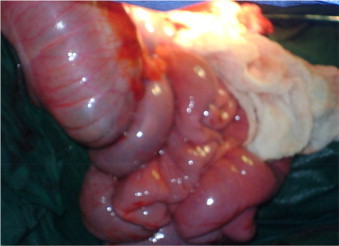

Ileosigmoid Knotting (ISK): Axial Twisting of the Ileum and Sigmoid Colon Around Each Other

Considered a “Compound” or “Double Volvulus” as Both Segments Twist Around Each Other (Knotted) Causing Closed Loop Obstruction of Both the Small and Large Intestine

Causes a Closed Loop Obstruction That Can Cause Vascular Compromise with Ischemia, Necrosis, and Perforation

• Type I: The Ileum (Active Component) Encircles the Sigmoid (Passive Component) – Most Common

• Type II: The Sigmoid (Active Component) Encircles the Ileum (Passive Component)